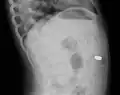

Peritoneum

Foreign bodies in the peritoneum can include retained surgical instruments after abdominal surgery. Rarely, an intrauterine device can perforate the uterine wall and enter the peritoneum.

Foreign bodies in the peritoneum eventually become contained in a foreign body granuloma. In the extremely rare case of retained ectopic pregnancy, this forms a lithopedion, which involves the fetus being too large to be reabsorbed, and is calcified[13] as a means of shielding the surrounding tissue from infection.